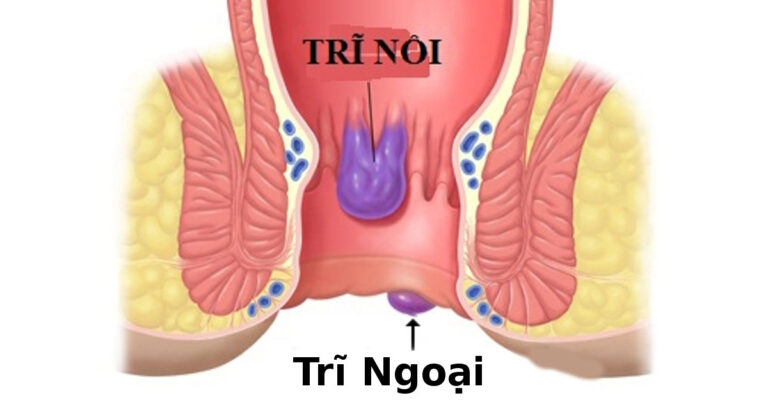

Trĩ Gây Thiếu Máu: Dấu Hiệu, Chi Phí & Phương Pháp Điều Trị Tại Tuyên Quang

Trĩ Gây Thiếu Máu: Nguyên Nhân, Dấu Hiệu Và Giải Pháp Điều Trị Trĩ gây thiếu máu là tình trạng nghiêm trọng xảy ra khi bệnh nhân bị…